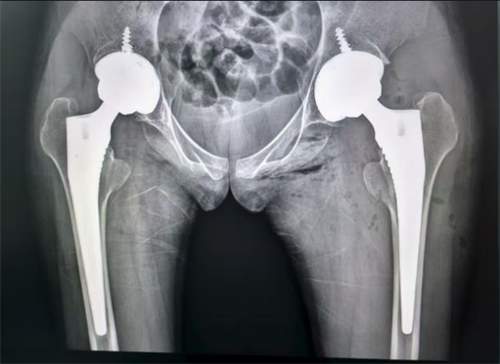

小雨进行左侧髋关节置换术后的X片

经过三个月的积极康复,右侧髋关节功能恢复良好,身体状态调整至最佳。今年9月初,李良军主任团队再次为她完成了左侧人工全髋关节置换术。两次手术都非常成功,出血少、恢复快,未出现任何并发症。目前小雨已经完全脱离了轮椅和拐杖,可以独自无痛行走,基本恢复了正常生活。